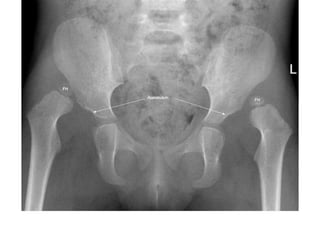

Asetabular açı

• Her iki Y kıkırdağını birleştiren Hilgenreiner çizgisi

• Bu çizgiye asetabulumun üst dış kenarı ile Y

kıkırdağı arasındaki ikinci çizgi

• İki doğru arasındaki açıya asetabular açı denir.

• Yenidoğanda bu açı ortalama 27.5 derecedir. 30

derecenin üzeri patolojiktir ve asetabular

displaziyi gösterir

Perkins kadranları

• Hilgenreiner çizgisine asetabulumun üst

kenarından bir dik çizgi çizilir. Alt-iç, alt-dış,

üst-dış ve üst-iç olmak üzere dört kadran

ortaya çıkar. Femur başı epifizinin normalde

alt-iç kadranda olması gerekir. Eğer alt-dış

kadranda gözüküyorsa sublukse kalça, üst-dış

kadranda ise disloke kalça denir

Asetabular açı • Heriki Y kıkırdağını birleştiren Hilgenreiner çizgisi • Bu çizgiye asetabulumun üst dış kenarı ile Y kıkırdağı arasındaki ikinci çizgi • İki doğru arasındaki açıya asetabular açı denir. • Yenidoğanda bu açı ortalama 27.5 derecedir. 30 derecenin üzeri patolojiktir ve asetabular displaziyi gösterir

Perkins kadranları • Hilgenreinerçizgisine asetabulumun üst kenarından bir dik çizgi çizilir. Alt-iç, alt-dış, üst-dış ve üst-iç olmak üzere dört kadran ortaya çıkar. Femur başı epifizinin normalde alt-iç kadranda olması gerekir. Eğer alt-dış kadranda gözüküyorsa sublukse kalça, üst-dış kadranda ise disloke kalça denir